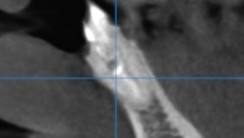

【フィステルから造影剤を挿入 病巣は根尖ではなく遠心側にある】

【CT画像でも遠心側に病巣】

【根尖には透過像がない】

【明らかに遠心側に透過像がある】